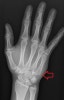

X-ray : (CMC joint dislocation and ligament injury)

- 무지 수근-중수 관절 손상(1st CMC joint injury)

- 제 2-5 수근 중수 관절 손상(2nd~5th CMC joint injury)